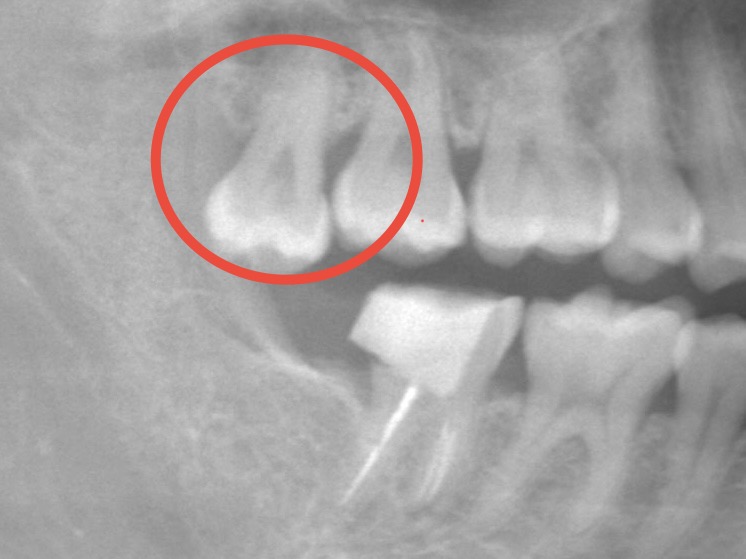

初診時の写真です。

大きく歯並びがずれている訳ではなく、前歯が少し前に出ている部分があるのと、がたつきがありきれいに並んでない部分があります。

しかし、噛み合わせには大きな問題点はなく、検査で得た資料を元に矯正医と相談し部分矯正での対応をおすすめしました。